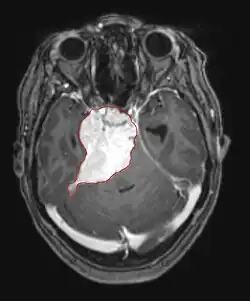

Imaging

• MRI

• Preferred imaging because it can show dural origin

• Dural tail sign seen in about two-thirds: characteristic marginal thickening that tapers peripherally along the dura

• Isointense on T1, hyperintense (usually homogeneously) on T2, strong enhancement with IV contrast